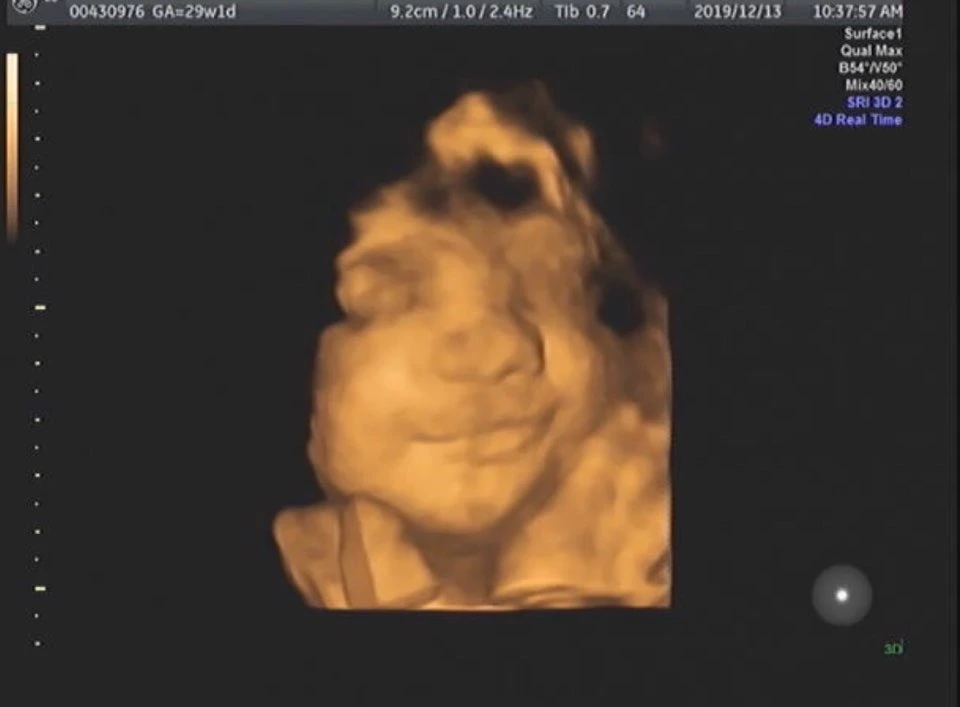

수많은 검사 중에 가장 기다렸던 입체 초음파를 봤다. 흑백이 아닌 입체로 완벽하진 않지만 지금 아기의 생김새를 볼 수 있는 아주 신기한 검사. 그러나 수줍어서인지, 비싸게 구는 타입인지 구석에 콕 박혀서 얼굴을 잘 보여주지 않았다. 병원 계단을 올랐다 내려오고, 한참을 걷고, 당수치를 걱정하면서 초콜릿을 먹고, 끊임없이 배를 움직이며 세 번의 시도 끝에 얼굴을 볼 수 있었다.

아기는 웃고 있었다. 볼은 통통하게 살이 올랐고, 턱은 딥플로우처럼 동그랗고 매끈했다. 내가 볼 땐 코도 꽤 높아 보였다(부모의 착각). 언젠가 꾸꾸가 가장 예뻤던 순간을 적으면, 상당히 앞쪽에 적히지 않을까 라는 마음이 들 만큼 예쁘고 사랑스러웠다. 기계로 문질러서 간지러웠나, 우리가 보는 걸 알고서 웃어줬나, 나의 바람대로 뱃속 생활이 즐겁나. 수많은 상상을 하며 하루에도 몇 번씩 사진을 꺼내본다. 이유가 무엇이든 행복해 보여서 보는 것만으로도 행복했다.